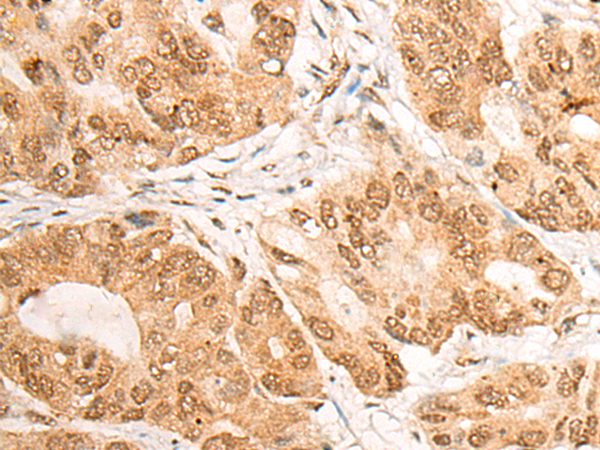

分类: 科研抗体货号: P06307别名: SUR2; CRSP3; MRT18; SUR-2; ARC130; CRSP130; CRSP133; DRIP130应用: IHC反应种属: Human, Mouse, Rat